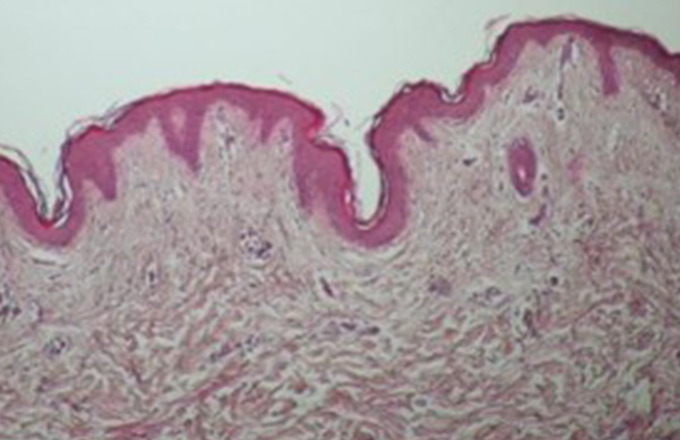

즉각적 타이트닝 + 콜라겐 리모델링에 의한

지속적 리프팅 효과